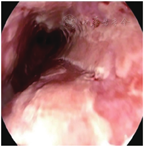

患者女,62岁,因吞咽时胸痛5 d,于2022年2月10日收入我院胃肠内科及消化内镜中心。患者5 d前出现吞咽时胸骨后刺痛,偶有反酸和上腹部隐痛,无放射痛、腹胀、恶心和呕吐。2 d前至我科门诊就诊,心电图未见异常,胃镜检查结果示食管距门齿20~37 cm处可见多处糜烂和多发浅溃疡,表面覆黄白苔,管腔通畅,贲门黏膜充血、色红,胃体黏膜光滑呈橘红色,液体量中等,胃角形态正常,胃窦黏膜局限性充血、色红,幽门变形,十二指肠球部及球后未见异常(图1)。取食管组织送病理检查。门诊诊断:食管溃疡,慢性非萎缩性胃炎伴胆汁反流。为明确病因收入院。患者否认口腔溃疡、肺结核、食管疾病等病史,否认药物、食物过敏史。